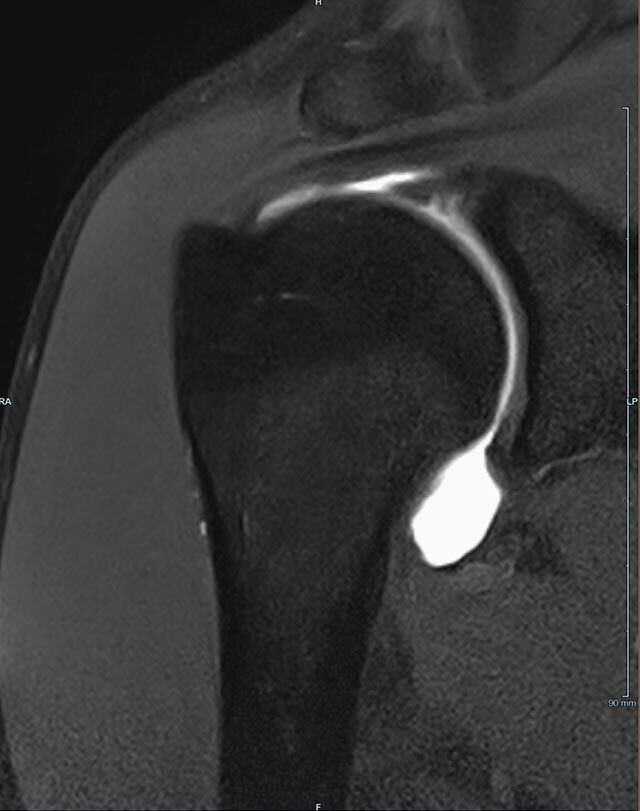

Gelenke

Hand

• Beurteilung von Knochen, Bändern und anderen Weichteilstrukturen der Gelenke nach Unfall.

• Arthrosediagnostik (Knorpelschaden)

• Impingement-Symptomatik

• Ursachenklärung bei wiederholter spontaner Gelenkluxation

• Ausbreitungsdiagnostik bei Gelenkentzündung, z.B. im Rahmen von rheumatischen Grunderkrankungen

Arthrographie

• MR-Arthrographie – nach örtlicher Betäubung und gründlicher Desinfektion der Haut wird unter Lagekontrolle mit Röntgen-Durchleuchtung eine kleine Nadel in den Gelenkraum positoniert und darüber ein MR-taugliches Kontrastmittel in den Gelenkraum gespritzt. Danach wird die Nadel entfernt. Anschließend erfolgt die MRT des Gelenkes. Diese Methode stellt kleine anatomische Strukturen des Gelenkraumes verbessert dar, z.B. zur Therapieplanung vor Arthroskopie bei Sportverletzungen der Schulter oder Gelenkinstabilität.